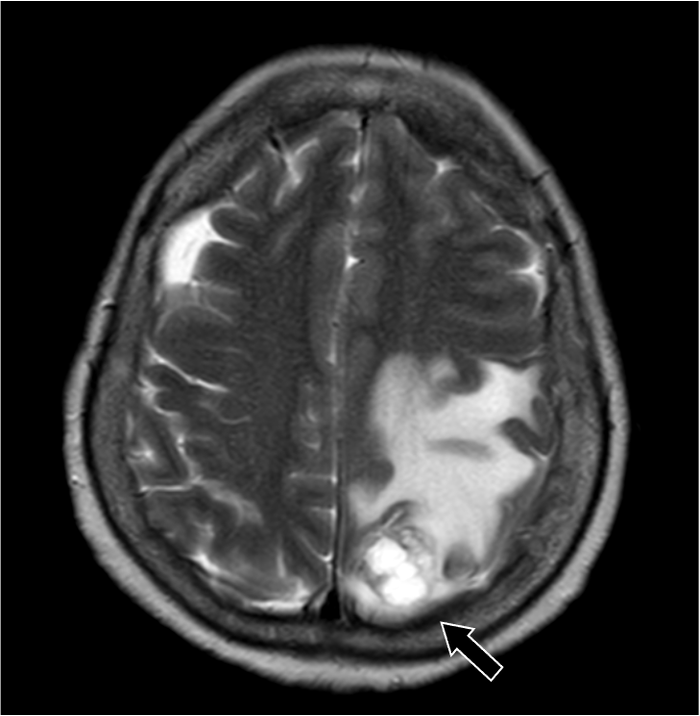

202X年より右手指知覚障害、頭痛を自覚。数日後から頻回嘔吐や右下肢運動障害があり、頭部造影MRIにて精査。既往に転移性肺腫瘤の治療歴あり。

症例解説

201X年腎細胞癌に対して手術を施行。術後経過で肺転移が出現。外科的切除および化学療法にて縮小を維持していた。202X年神経症状が出現し、頭部造影MRIにて左頭頂葉の孤発性脳転移と診断された。開頭腫瘍摘出術および定位照射を行い、再発なく経過している。

造影MRI検査は単純MRI検査と比較して、追加病変の検出能や診断精度の向上が示されている。造影MRI検査は、非腫瘍性白質疾患(慢性微小血管虚血性疾患など)を転移性腫瘍と鑑別する上でも有用である。脳腫瘍では腫瘍周囲に血管原性浮腫を認める場合があるが、高悪性度の原発性脳腫瘍と比較して、転移性脳腫瘍では腫瘍径に対する血管原性浮腫の面積が広いことが報告されている。単純MRI検査では腫瘍径を過大評価する可能性があり、術前・放射線治療計画等に際して造影MRI検査による適切な評価が求められる。